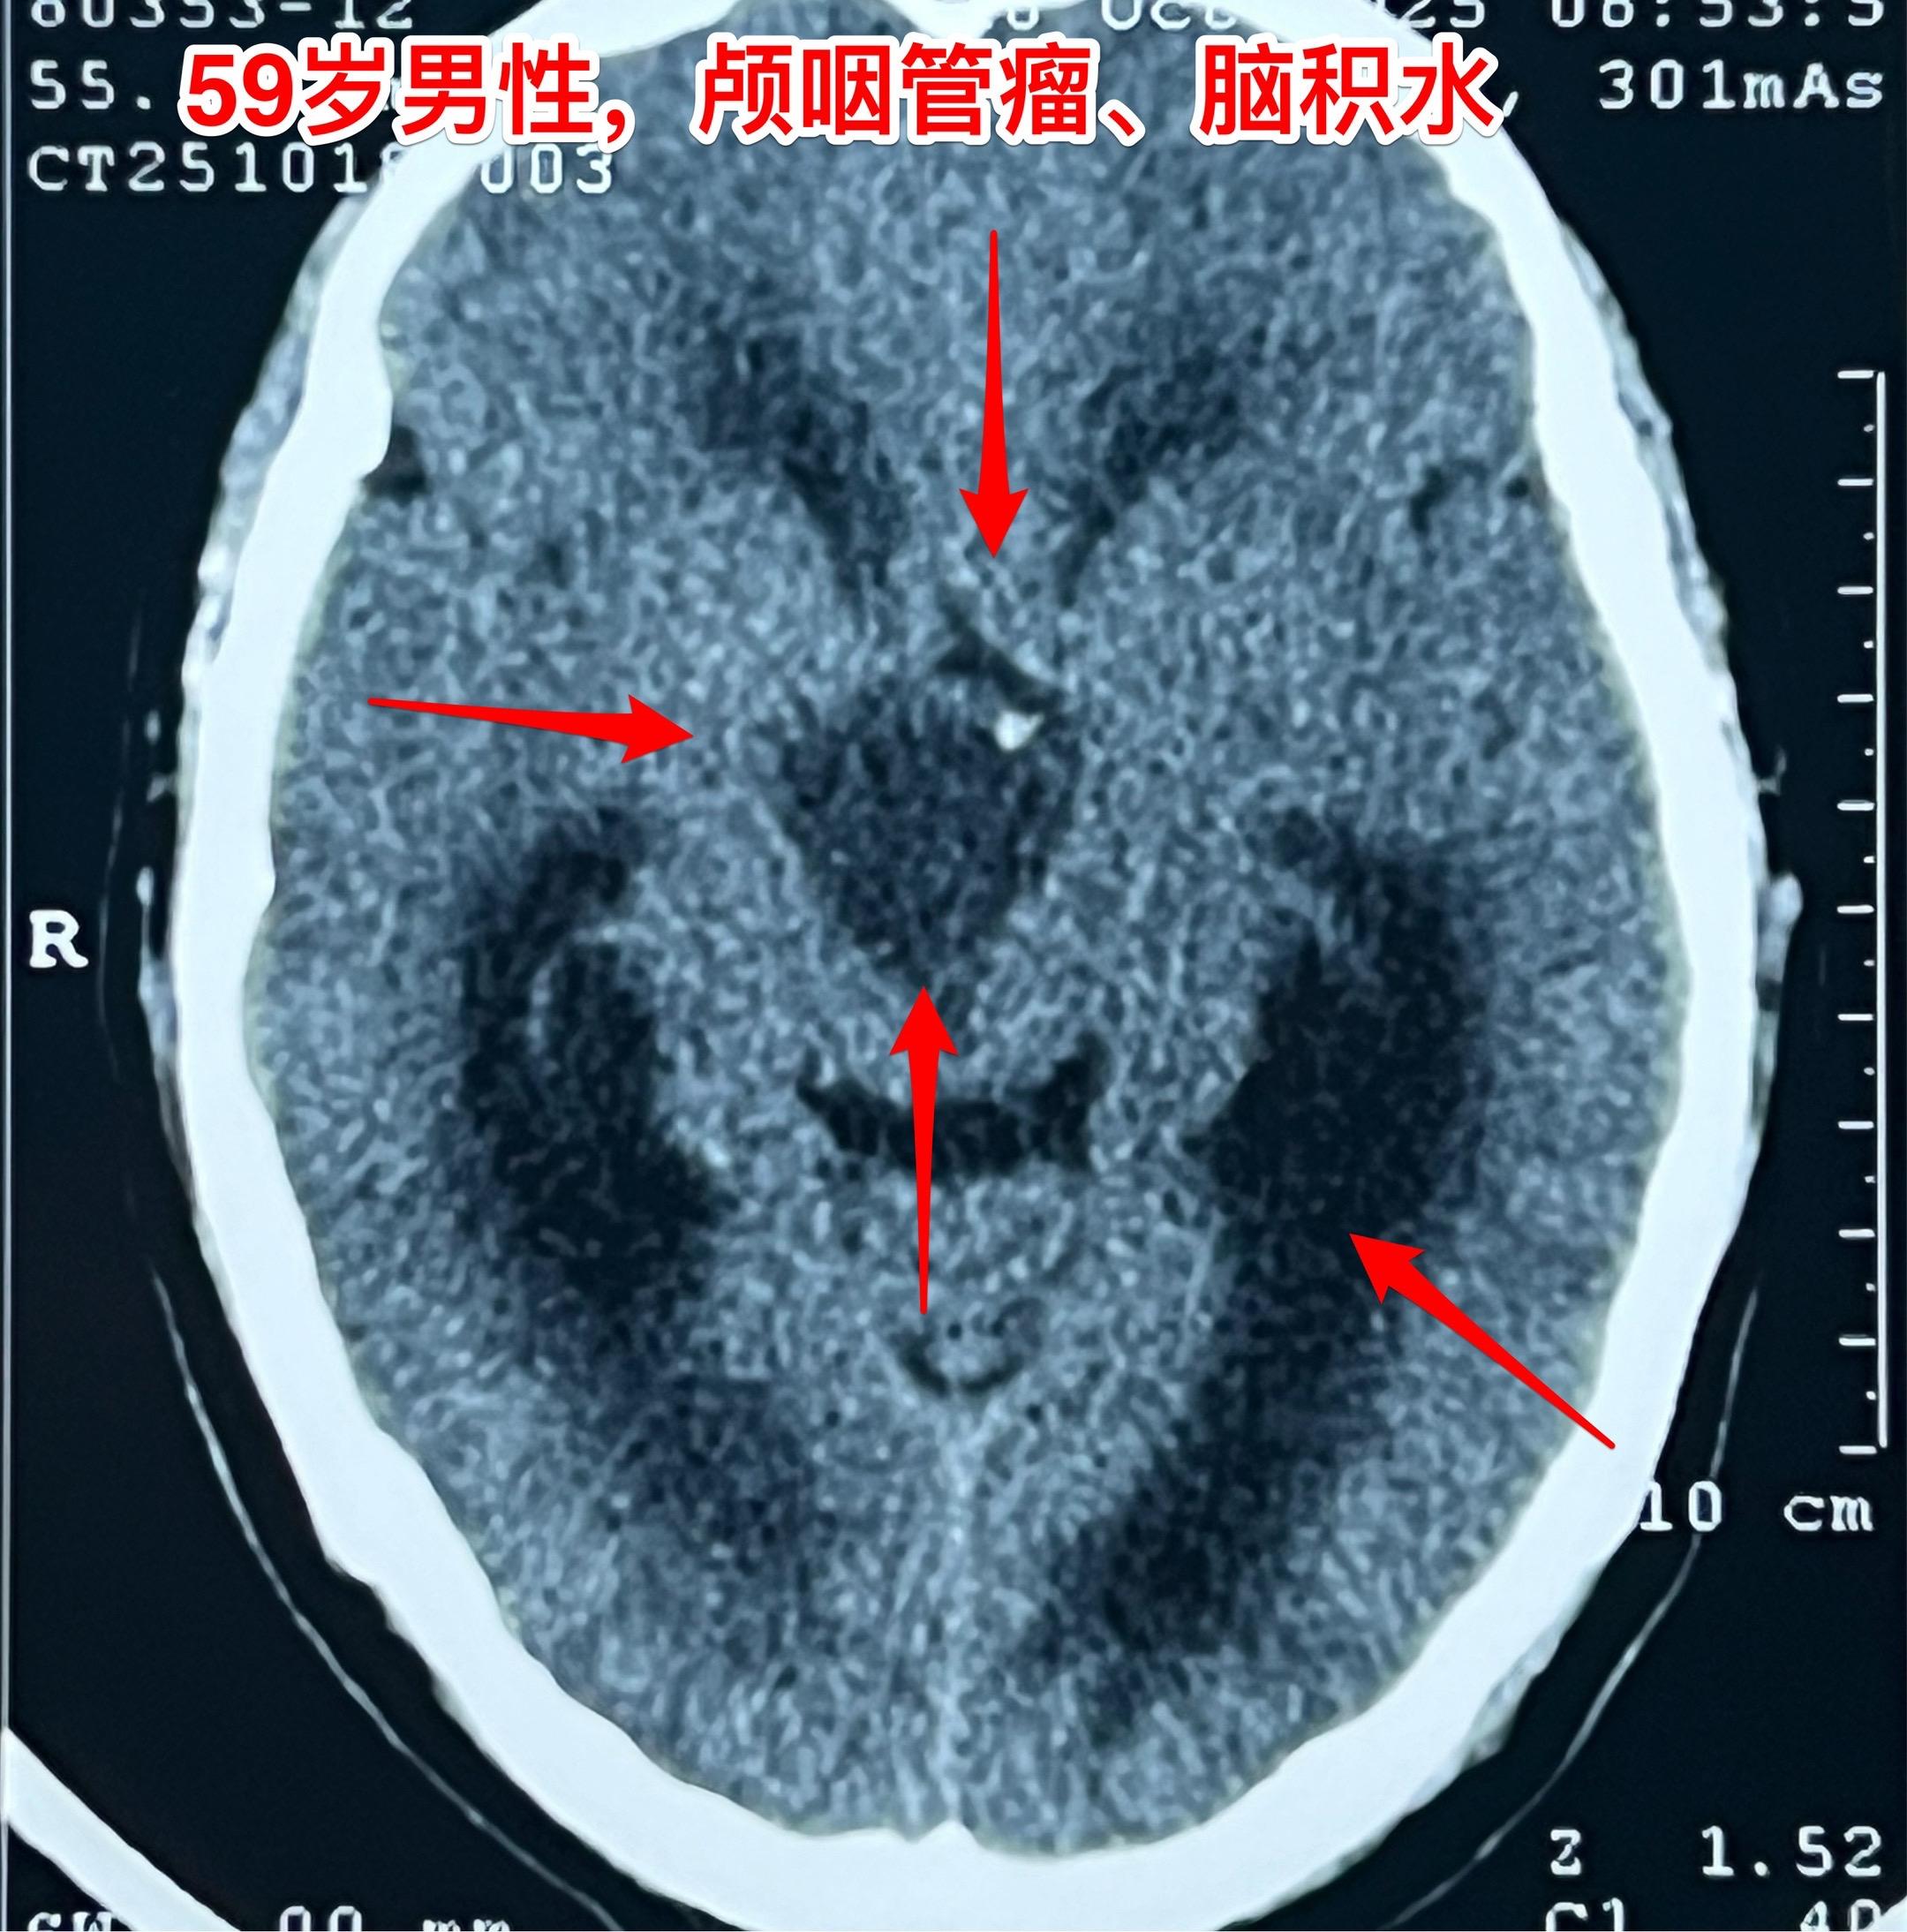

周日加班完成两台颅咽管瘤手术(第167)2025年10月26日(周日)完成了今年的第167例、168例颅咽管瘤手术。 第167例病人,59岁男性,甘肃省武威市人,因视力下降、思维糊涂到医院检查发现颅咽管瘤。 第168例颅咽管瘤患者是15岁的男生,江西省南昌市人,有头痛症状、视力下降症状,但是并未就医。偶然因骑自行车与别人相撞,到医院作头部CT才发现了这个颅咽管瘤。 这两个手术都不简单,肿瘤位置稍有不同,颅咽管瘤均得到完全切除。今天看见两个病人的精神状态均好!